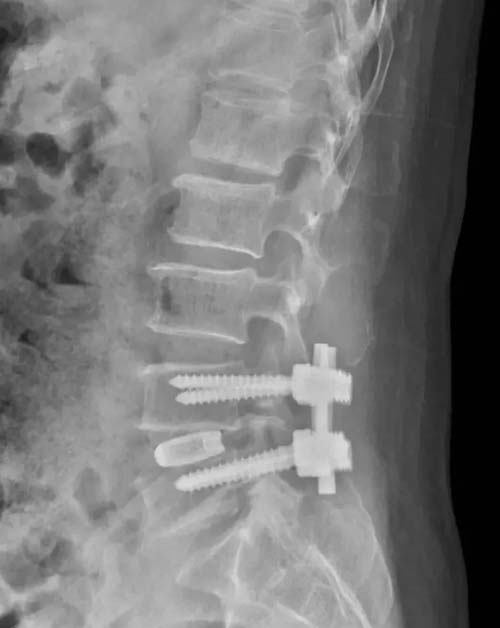

腰椎病例是66岁女性患者,主诉“腰痛10余年,加重5年,双下肢疼痛4年”。查体显示腰椎屈曲活动受限,腰部棘突,椎旁肌无明显压痛,叩击痛。腰椎MRI显示L4/5椎间盘突出并黄韧带肥厚并椎管狭窄。诊断为腰椎管狭窄症,腰椎间盘突出症,高血压病,Ⅱ型糖尿病。

该患者为腰椎间盘突出所致椎管狭窄,L4/5椎间隙退变严重,需要进行腰椎减压椎间融合手术,需要近期的可靠稳定及远期的牢固融合。这种腰椎融合手术一般应用不同规格的PEEK材料椎间融合器,因其椎间融合器上下仅两面植骨及通体无微孔结构,骨接触面积小,术中即刻稳定性及术后远期骨性融合效果往往不佳。丰荣杰主任医师决定为患者采用3D打印钛合金椎间融合器,进行腰椎后路减压植骨融合内固定术。该手术可在融合器前后左右360°以及上下两个面与椎体终板及周围骨质形成全方位无间隙的融合,有效增加骨接触面积,利于自体骨的长入。同时,3D打印钛合金融合器更加接近人体正常骨质的弹性模量,有效避免应力遮挡及骨吸收,与人体骨质有效融合,获得良好的即刻稳定性和远期的牢固骨性融合效果,避免骨性不融合、断钉、断棒等并发症的发生,进一步增加手术效果及手术安全性。

术前X线

术后X线